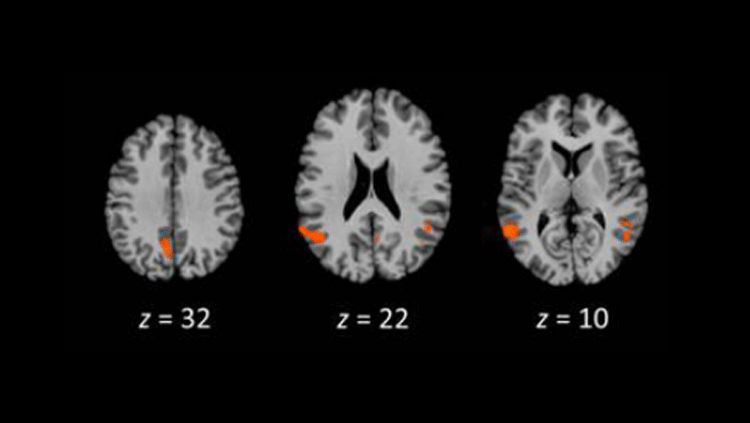

Mouse models expressing human ACE2 display infections in the brain. Source: Sun, S., Et al. (2020). A Mouse Model of SARS-CoV-2 Infection and Pathogenesis. Cell Host & Microbe, 28(1) 124-133.e4. doi: 10.1016/j.chom.2020.05.020

“It's sort of a window into the brain because it’s something you can relatively easily access,” says Marco Hefti, a neuropathologist at The University of Iowa in Iowa City. The nose can also be a pathway into the brain for viruses, he says. It’s not clear if in rare cases, SARS-CoV-2 might be able to hop from the nose to the brain as scientists believe happens in other viruses, like chikungunya, polio and other human coronaviruses, which don’t target ACE2. In one study SARS-CoV-2 nasal exposure led to infection in the brain in a mouse model expressing human ACE2 where mouse Ace2 is normally present. But little evidence exists for this happening in humans.